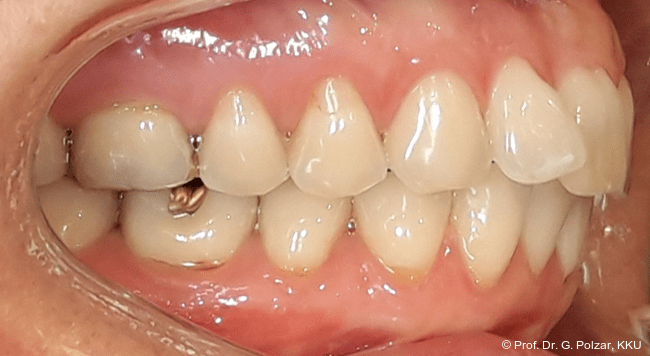

Der intraorale Befund zeigte eine scheinbar neutrale Verzahnung. Trotz Lingualretainer in der UK-Front war ein Engstand in der Unterkieferfront mit leichter Protrusion erkennbar. Appro­ximal des Zahnes 41 waren deutliche schwarze Dreiecke zu erkennen, zudem wies der Zahn eine leichte gingivale Rezession auf (Abb. 3a–f).

Die 38-jährige Patientin stellte sich 2019 zum ersten Mal in der Praxis vor. Nach einer drei­jährigen kieferorthopädischen Behandlung im Jugendalter mit Multibandapparaturen kam es im Laufe der Zeit zu einem Rezidiv mit Retro­inklination der oberen mittleren Frontzähne. Der Wunsch der Patientin war es, „wieder gerade Zähne“ zu haben. Die sehr gesundheitsbewusste Patientin hatte sich im Vorfeld von 14 kieferorthopädisch tätigen Kollegen beraten lassen, war aber von den vorgeschlagenen Therapiemaßnahmen nicht überzeugt (Abb. 1a–d).